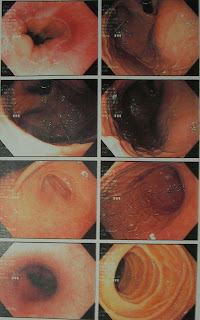

April 7: After experiencing digestive issues over the past few months, my GI decided to schedule me for a EGD (upper GI scope). I asked for a copy of my images to share, the results showed that I have a hiatal hernia which is causing the reflux. This is actually good news because it means that I don’t have an ulcer!